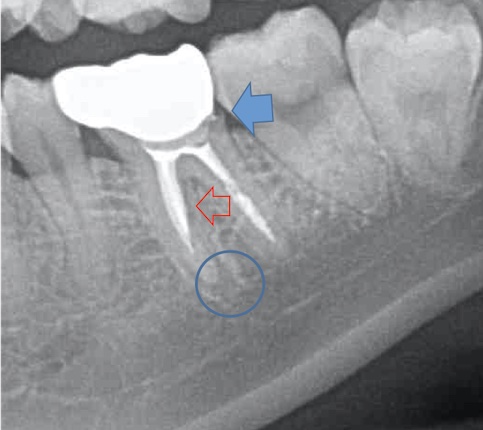

かぶせ物が不適であること(青矢印部)、近心根に根尖病巣があること(青枠部)、根充剤がかなり太いため(赤矢印部)歯質が薄くなっていることなど問題点がいくつかありましたが、他院で治療をしたばかりであり、また上記の条件から再治療には抜歯のリスクが非常に高いことから初診時は患者さんと相談し経過観察することになりました。